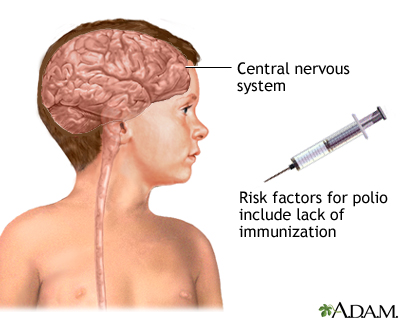

Poliomyelitis

Poliomyelitis is commonly known as polio. The disease is caused by a virus called poliovirus and can lead to paralyzing nerve damage, which can be fatal or lead to lifetime disability. Polio was a major killer of children in the early 20th century. Vaccination programs have eliminated the disease in most parts of the world. But cases still occur in certain parts of Asia and Africa. Vaccination is still recommended because there is still a risk of acquiring polio through international travel.

Poliomyelitis is a communicable disease caused by viral infection and occurs through direct contact with infected secretions. Polio is found worldwide, but immunization has reduced the incidence. Clinical polio affects the central nervous system (brain and spinal cord). Disability is more common than death.